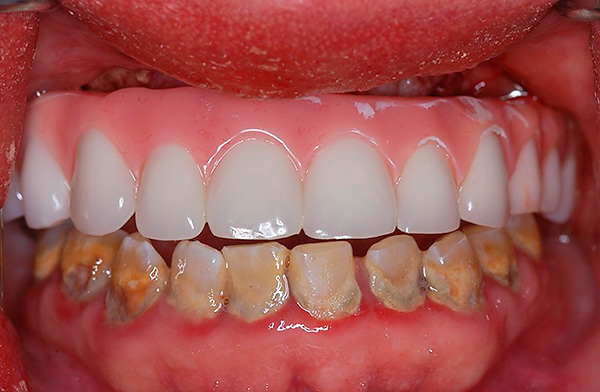

Deve-se ter em mente que o conceito de "implantação basal", como tal, hoje é coisa do passado. Existe um protocolo de carregamento imediato, que inclui várias tecnologias para restauração dentária, dependendo do quadro clínico. É adequado para restaurações simples e múltiplas, incluindo a ausência completa de dentes - um exemplo correspondente é mostrado nas fotografias abaixo:

É por isso que você não deve confiar cegamente na publicidade de clínicas odontológicas que oferecem implante basal - você deve necessariamente pesar os prós e contras, verificar os atestados médicos e observar os resultados de suas habilidades práticas (por exemplo, examine fotos com exemplos mostrando a cavidade oral dos pacientes antes e depois do tratamento) .